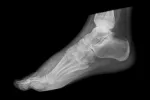

Fascitis plantar

La fascia plantar es una banda de tejido elástica situada en la planta del pie, que amortigua el impacto que se produce al caminar. El deporte, el exceso de peso, o un calzado inadecuado, pueden dañarla.